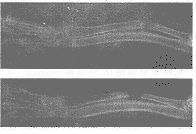

【摘 要】 目的 观察经皮自体骨髓移植在骨缺损瘢痕组织内的成骨作用 ,探索治疗骨不连的新途径。方法 选健康家兔18只,建立双侧桡 骨中段骨及骨膜缺损1cm模型,6周后,实验侧(右)骨缺损区经皮注射自体红骨髓2ml,对 照侧(左)骨缺损区经皮注射自身外周血2ml。在不同时间内进行X线片、组织学检查及新生 组织钙、磷含量测定。临床应用经皮自体骨髓移植治疗骨不连15例,其中腕舟骨不连7例, 肱 骨不连3例,股骨不连2例,胫骨不连3例。骨不连时间为7~48个月,平均13个月。结果 实验侧骨缺损区在骨髓注射后不同时间的X线片、组织学检查均显示新 骨 形成逐渐增多,钙、磷含量均高于对照侧。对照侧无成骨现象。临床应用的15例中,13例在 5~9个月骨折愈合,2例未愈合。结论 经皮自体骨髓移植在骨缺损 瘢痕组织内有成骨作用,在临床上可作为治疗骨不连的方法,尤其适用于骨不连部位软组织 条件差、不具备开放植骨的病例。

【Abstract】 Objective To observe the osteogenesis of percutaneous autogenous bone marrow grafting in cicatricial bone defect,to seek a good method for treating fracture nonunion.[ WT5 ”HZ〗Methods Eighteen rabbits were adopted in this study.1 cm bone defect model was made in each side of radius, 6 weeks later,2 ml autogenous bon e marrow was injected in the right radial bone defect as experimental group,2 ml autogenous peripheral blood in the left side as control group. X-ray featu res,histologic changes, Ca and P content in the site of bone defect were studied in various times.Also 15 patients were treated clinically for the nonunion frac t ure,the average time from nonunion to bone marrow grafting was 13 months.Results In experimental group, the increasing new bone tissue we re observed in X-ray and histologic examination.While in control group, no oste ogenesis was observed.Ca and P content of experimental group was higher than tha t of control group.For the 15 patients ,13 cases healed in 5~9 months,2 cases f ailed.Conclusion Percutaneous autogenous bone marrow gra fting is capable of osteog enesis in the cicatricial bone defects.It can be used in nonunion cases which ar e not fit for operation of bone grafting because of poor condition of the skin.